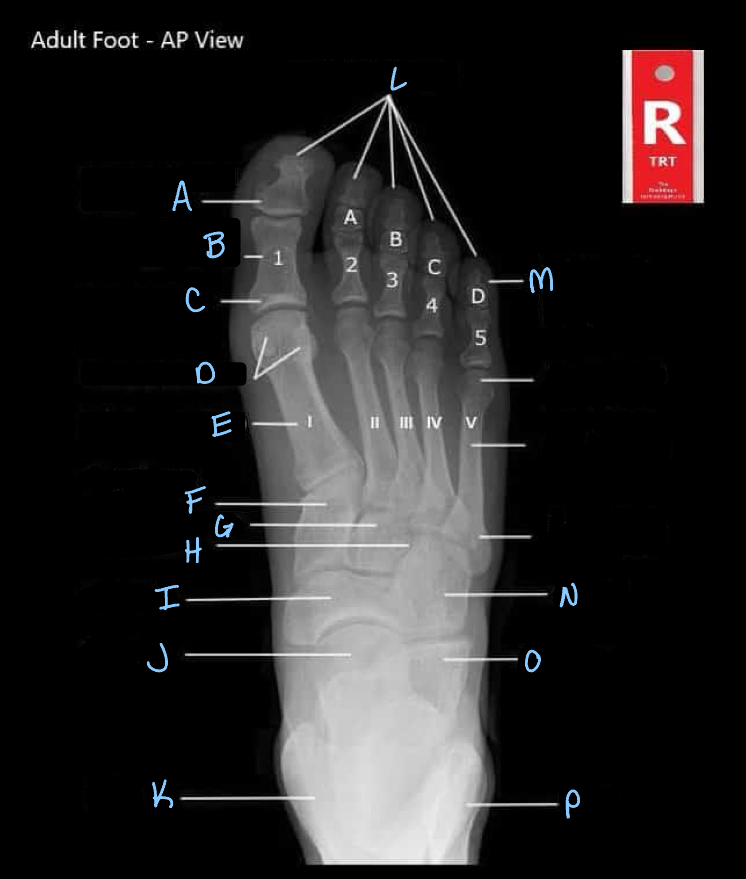

What is A?

interphalangeal joint

16

What is B?

proximal phalanges

17

What is C?

metatarsophalangeal joints

18

Q

What is D?

A

sesamoid bones

19

What is E?

20

What is F?

medial cuneiform

21

What is G?

intermediate cuneiform

22

What is H?

lateral cuneiform

23

What is I?

24

What is J?

25

What is K?

tibia

26

What is L?

distal phalanges

27

What is M?

intermediate phalanges

28

What is N?

cuboid

29

What is O?

calcaneum

30

What is P?

fibula